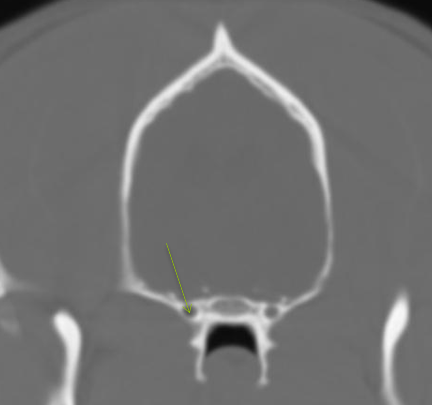

alar canal